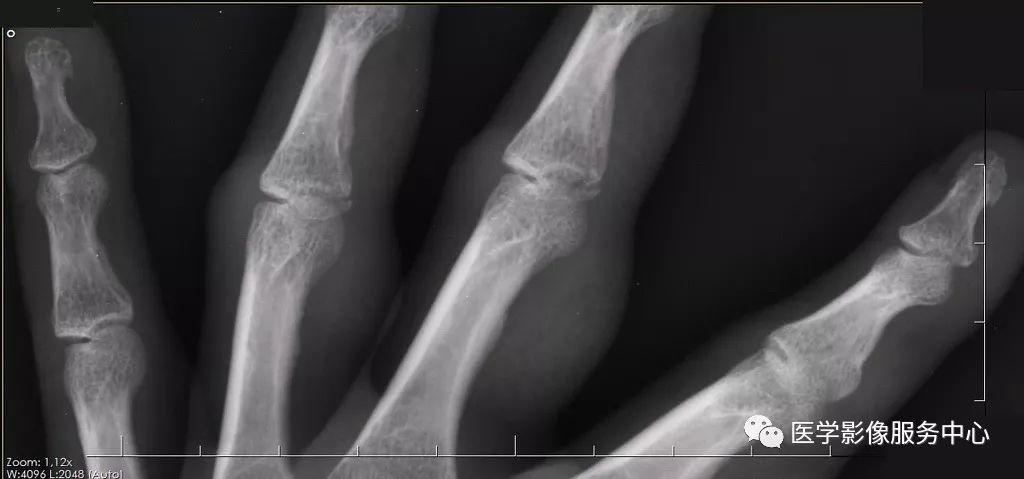

再看斜位片

这张斜位片有没有问题,有几处问题?

最后再看局部放大的斜位片,估计这时候大家都能够发现问题所在

2、标准的摄片摆位很重要

标准的摄片摆位是正确诊断的前提。但在实际工作中,由于患者伤处疼痛,往往配合不佳。这时候技术员朋友需要尽量的按照标准体位摆放,多给患者一些准备时间,不要因为可能会耽误时间而应付了事。以本病为例,正位片很难看到骨折线影,只有在斜位片才能够清楚发现两处骨折。假如患者因为疼痛,斜位摆放位置不佳,有可能将骨折线遮掩,从而得不到正确的检查结果。

一个称职的影像诊断医生,要注意影像的蛛丝马迹。本病例的正位片虽然看不到明显的骨折线影,但是第四近节指间关节周围软组织还是可以发现肿胀。斜位片更加明显,第三、第四近节指间关节周围软组织均可发现肿胀,这就给我们一个提示。这时候要仔细查看该处有无骨折存在。这种间接征象对影像诊断有很大帮助。此外,正位片看不到异常,不代表没有问题,有时我们的诊断同行正位片没发现异常,很自信的认为没有问题,匆匆扫一眼斜位片,然后直接得出未见骨折的错误诊断。正位片与斜位片都很重要,要结合看,这也是影像检查要拍摄正位及斜位的原因。